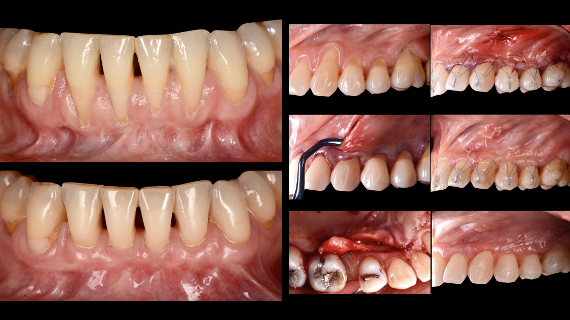

As recessões gengivais são uma das condições periodontais encontradas com maior prevalência na prática clínica diária. Assumem grande relevância, não só do ponto de vista estético, como também pelos problemas orais que normalmente envolvem.

A presente apresentação visa abordar as indicações para o tratamento das recessões gengivais, bem como os critérios que devem suportar a seleção da técnica cirúrgica no tratamento de recessões localizadas e generalizadas.